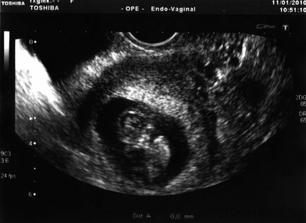

14.11.2009 OPU odebráno 7 vajíček,ET 16.11. zavedena 2 embrya a teď jen čekat,26.11. hlásíme //.3.12. hcg 1017mlU tak snad to konečně vyšlo.Uz naplánován na 8.12. jsme 5+4tt pan doktor je moc spokojen a další návštěla CAR je 22.12. mělo by být vydět srdíčko,tak snad vše dopadne dobře.Srdíčko v pořádku a mrňousek také,byli jsme předáni do péče gynekologa a loučení s CARem bylo těžší než jsem si myslela.

11.1. návštěva gynekologa,krásný uz prcek se točil nahoru a dolů,no prostě paráda,vystavena těhotenská průkazka a další kontrola 25.1. (vyšetření vrozených vad).

22.12. kontrolní UZ srdíčko krásně bouchá s manželem jsme to obrečeli a dostali jsme ten nejkrásnější dáreček od Ježíška.Byli jsme předáni do péče gynekologa.